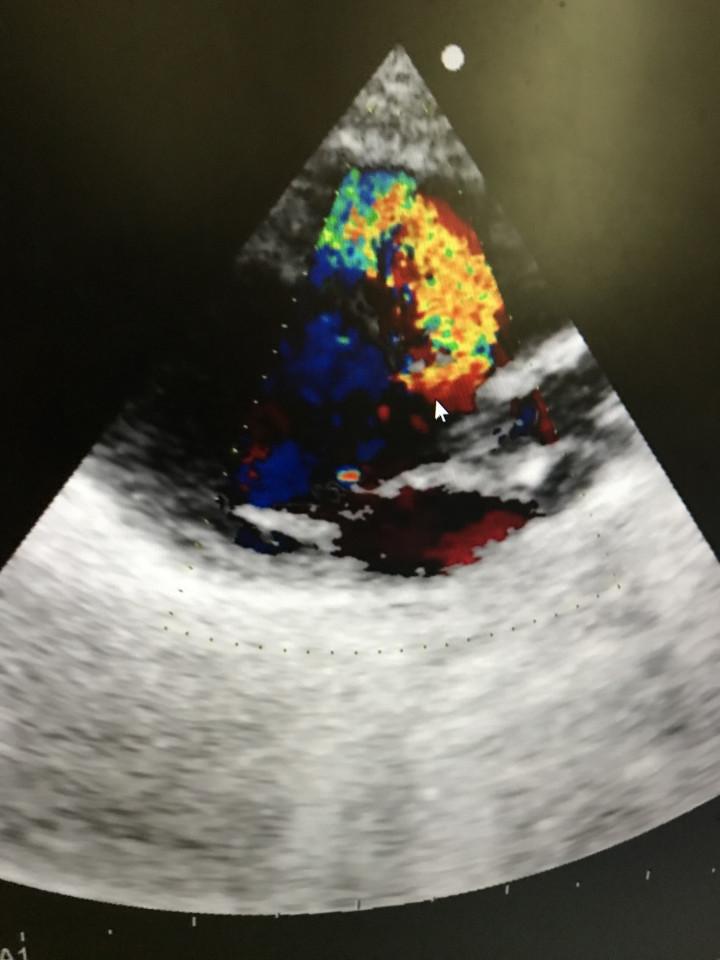

病気発覚当時のメルの心臓のエコー写真。

黄色と緑に見えるのが、本来流れ出てはいけない血液。

大量に流れ出てしまい、状態はかなり悪かったです。